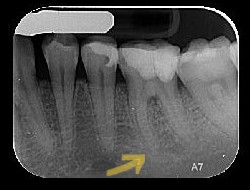

בתמונה ליד- צילום של שן שעברה VPT

לפני

המטופלת סבלה מכאבים מאוד חזקים בשן, מעירים משינה. על פי דרכי הטיפול המסורתיות, היה צריך לבצע טיפול שורש בשן. הוחלט לנסות להימנע מטיפול שורש. כיום, 10 שנים אחרי, זו השן היציבה ביותר בפה של המטופלת הזו

אחרי

בתמונה אחרי 10 שנים, ניתן לראות הסתיידות כמעט מלאה של תעלות השורש. ברגע שהוסר הגורם המזהם , בוצע כיפוי מוך (תחת תנאים מסוימים, כפי שמצוין במחקרים עדכניים), הונחה משחה המעודדת יצירת דנטין שלישוני. תאי מוך השן הצליחו לאטום את השורש באופן טבעי מבפנים, בלי התערבות שלנו ועם גיוס מירבי של מערכת החיסון.